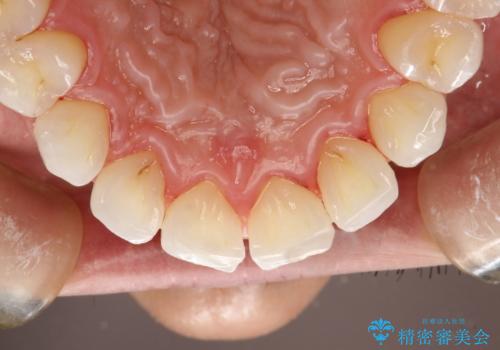

PMTCでお口のメンテナンス

- 痛みや特に気になるところはないが、しっかりとクリーニングしてほしいとのことで来院された患者様です。PMTC 30分コースでのメンテナンスを行いました。

歯を長持ちさせるために、1番の対策が、PMTC を定期的に行うことです。虫歯や歯周病の予防・再発の予防などと、患者様の歯の健康を保つためプロフェッショナルクリーニングを行っています。

痛みや症状が無くても、歯科医院にて専門的なクリーニングを行うことが大切です。